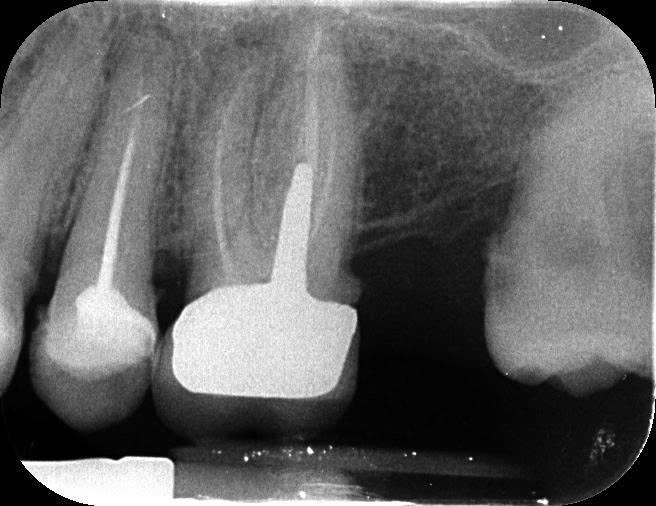

Прикладываю также прицельный снимок 46 зуба (в центре на центральном снимке) и 25 зуба (верхний левый второй премоляр, на прицельном снимке крайний слева) 7-месячной давности (27 февраля 2025 года).

- На 25 зубе (верхний левый второй премоляр) надо ли перелечивать каналы или просто поставить пломбу?

"На 25 зубе (верхний левый второй премоляр) надо ли перелечивать каналы или просто поставить пломбу?: я бы перелечил...